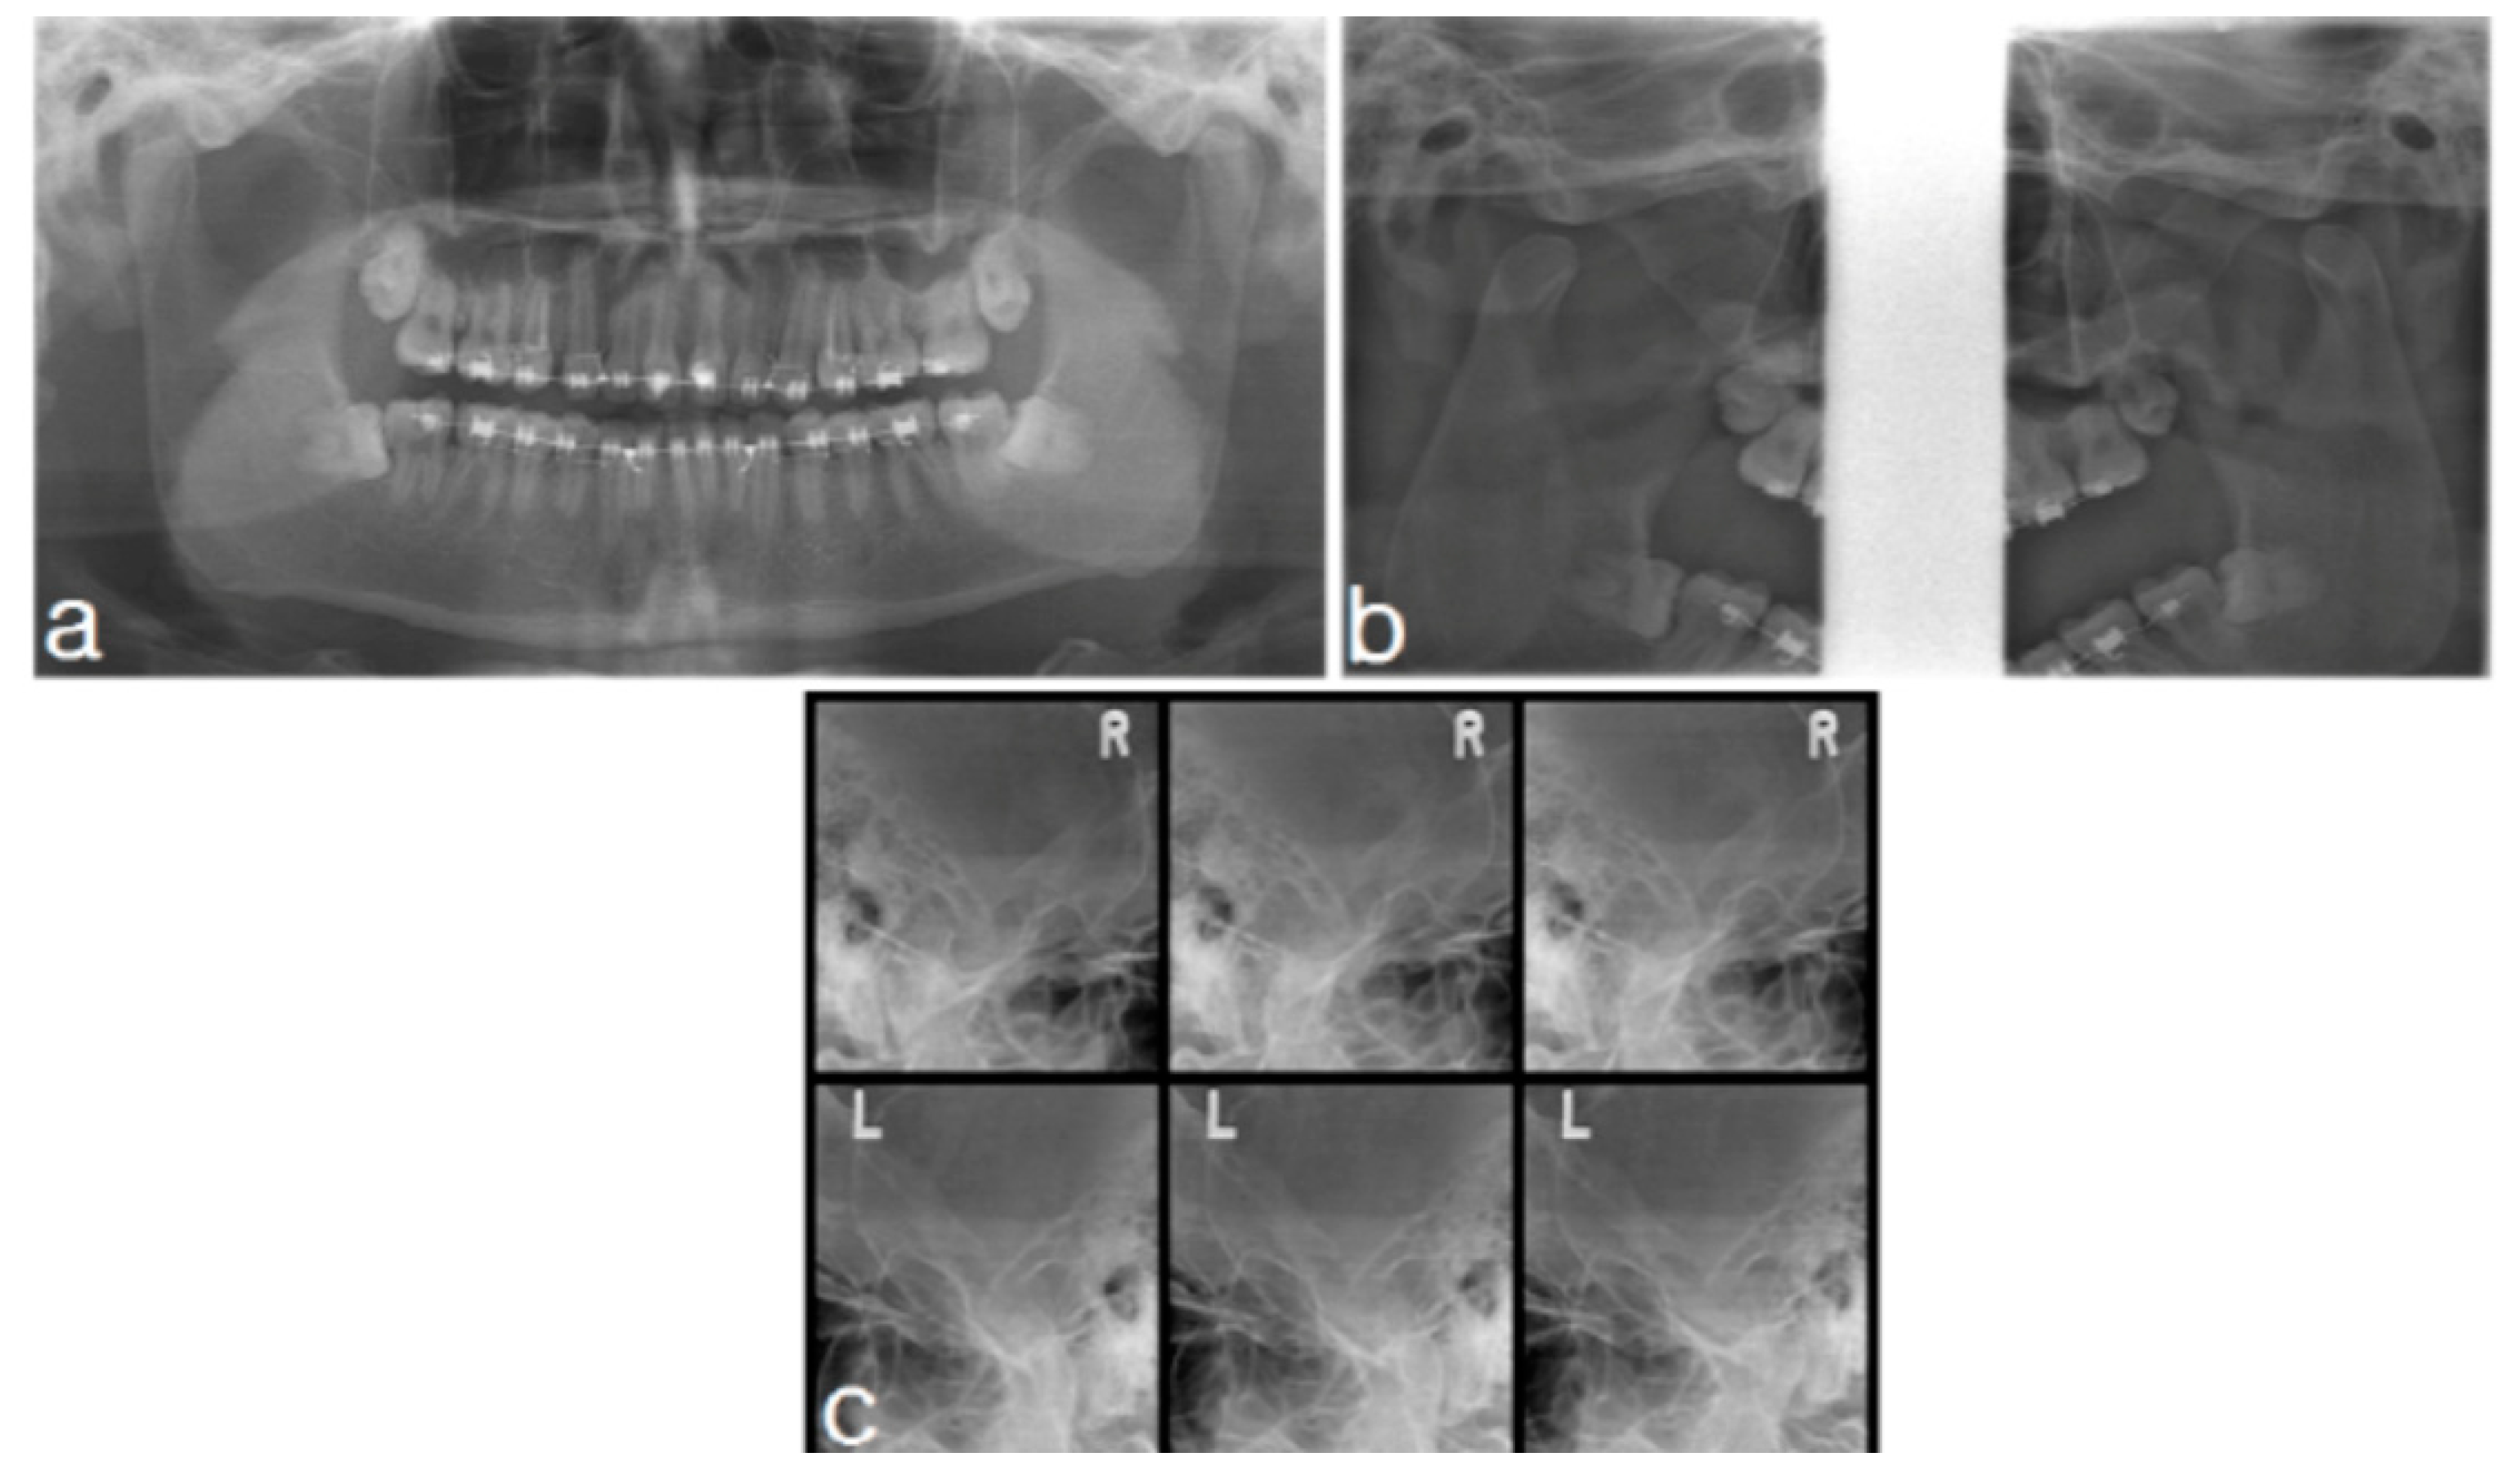

2.1.2. Imaging

2.2.2. Imaging